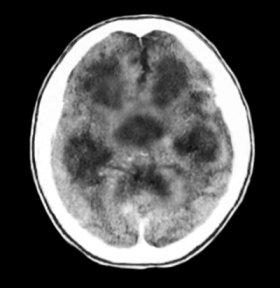

뇌수막염으로 교통성 수두증이 생긴 소아의 뇌 CT